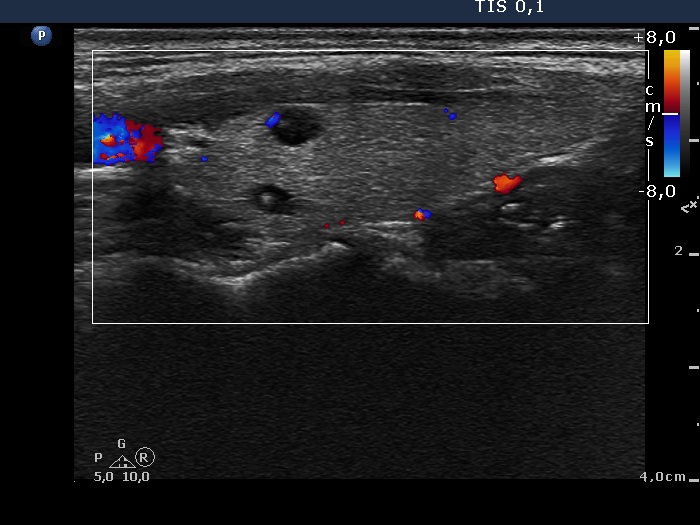

Intranodular hyperechogenic figures - case 402 (ultrasonographic picture 7)

Left lobe, longitudinal scan, color Doppler mode. The vascularization has no relevance in such cases.